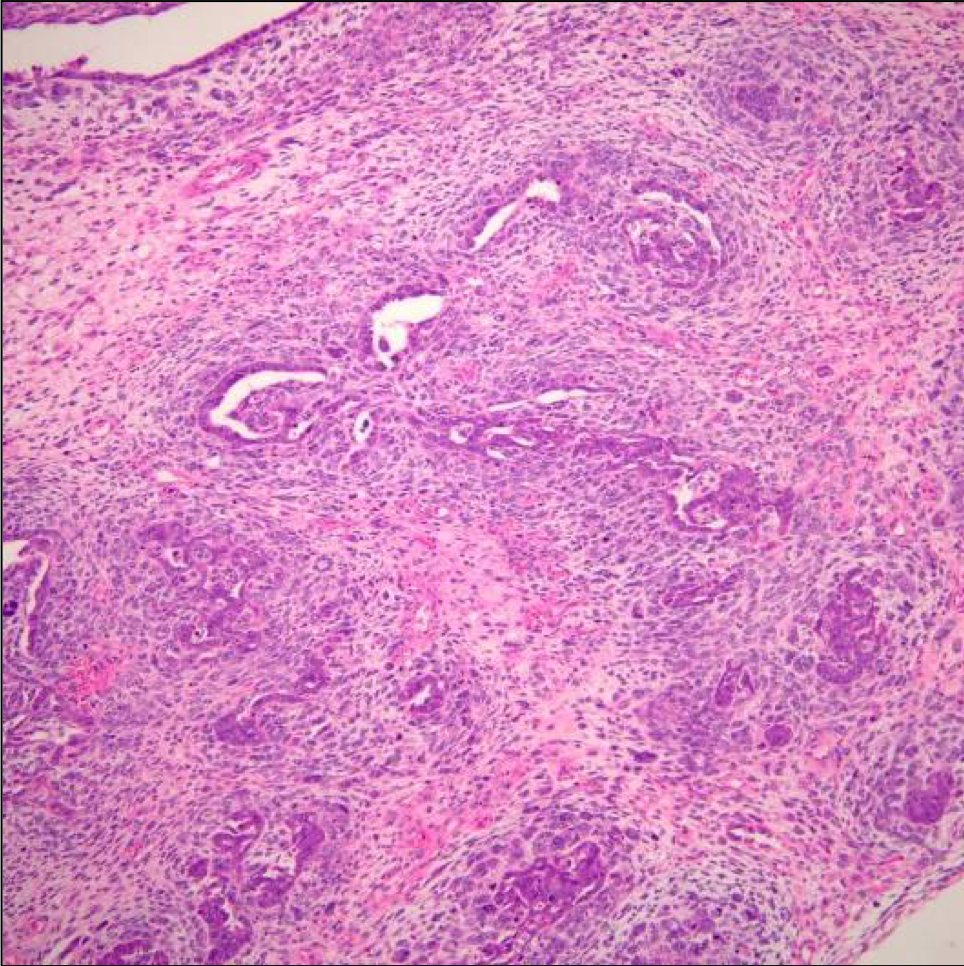

A 64 year-old man with history of clear cell renal cell carcinoma s/p nephrectomy (2021) presents with scrotal pain and firmness. Ultrasound reveals a 2 cm solid lesion. Serum tumor markers (hCG and AFP) were normal. The tumor was negative for SALL4, OCT3/4, AFP, and showed focal patchy positivity for pancytokeratin (focal). PAX8 was weakly positive. Additional stains are displayed in the pictures.